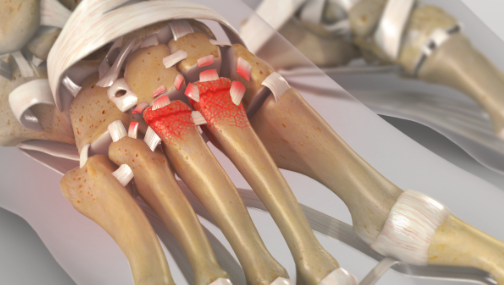

Joints are covered by articular cartilage which allows a bone to glide over another without symptoms. In the case of arthritis this covering is lost with the bones grinding and subsequent pain.